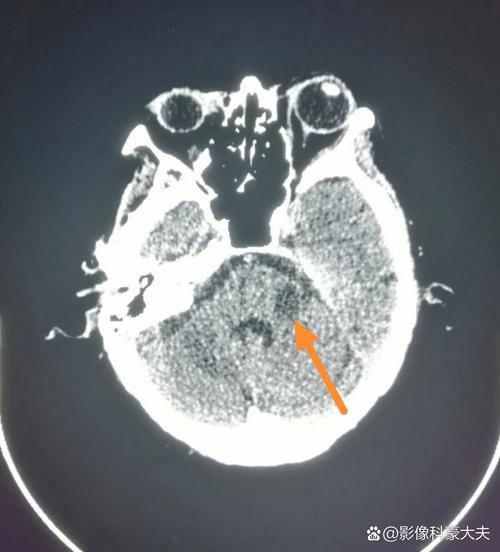

患者有脑梗死的症状和体征,但头颅CT检查没有显示出脑梗死的典型改变。

这并不排除脑梗死的诊断,反而高度提示超早期脑梗死,CT在发病后的几个小时内对脑梗死的敏感性不高,这是正常现象。

头颅CT主要是通过看脑组织的密度变化来发现问题的,脑梗死的发生和发展有其时间规律,而CT影像上的异常变化会滞后于这个时间过程。

- 发病6小时内(超早期):这是脑梗死治疗的“黄金时间窗”,在这个阶段,脑细胞刚刚开始缺血缺氧,细胞水肿非常轻微,CT上几乎看不到任何密度改变,即使已经发生了血管堵塞,CT报告也可能完全正常。这是最常见的情况。

- 发病6-24小时(早期):此时脑细胞水肿开始变得明显,CT上可能看到局部脑组织密度轻微降低,但界限不清,经验不丰富的放射科医生也可能漏诊或无法确定。

- 发病24-72小时(急性期):此时缺血区域的脑组织因为细胞坏死和水肿,在CT上会显示为清晰的、边界相对清楚的低密度影,这是CT诊断脑梗死最敏感的时期之一。